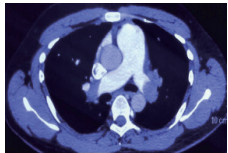

例4 62岁,女性,主诉“活动后气短20 d,加重1 d伴晕厥1次”。患者入院20 d前上近20级台阶后感气促,休息后缓解,未重视。入院前1 d,突发晕厥伴有轻微活动后明显的呼吸困难。既往:左下肢静脉曲张病史3~4年;入院40 d前患者左足跖骨骨折,接受外固定,尚未影响日常活动,未接受抗凝治疗;发现血小板减少数年(血小板维持5.5~8.6 g/L,末次于一年前血小板85 G/L),未明确原因及治疗;血气分析提示pH 7.447,PaCO2 32.2 mmHg,PaO2 85.3 mmHg,SaO2 96.8%;D-Dimer 1 947 ng/mL;FDP 22.84 μg/mL,FBG 2.05 g/L;PLT 51G/L;cTnI 0.52 ng/mL,BNP 299 pg/mL;ALT 318 U/L,AST 300 U/L,CREA 74.8 μmol/L,血Na+、K+、Cl-:正常范围;UCG提示:右心大,肺动脉主干轻度增宽(28 mm),三尖瓣反流(重度),反流面积13.7 cm2,TI法估计SPAP为30 mmHg、左室舒末内径35 mm、左室舒张功能受限(E/A 1:1.5)、未见节段性室壁运动障碍;双下肢静脉超声提示左侧腘静脉不完全血栓。心电图(图 12所示)提示窦性心动过速、SⅠQⅢTⅢ;CTPA显示肺动脉分叉处及双肺亚段充盈缺损(图 13所示)。

| 图 13 入院时CTPA结果显示肺动脉分叉处及双肺亚段充盈缺损 |

入院查体:神志清楚,体温36.5℃,血压120/70 mmHg,脉率110次/min,呼吸22~26次/min,指氧饱和度93%(安静,空气氧),未见乏氧征。双肺呼吸音清,未闻及干湿性啰音,心率110次/min,律齐,P2 > A2,心界无扩大,无杂音,腹软,无压痛,肠鸣音正常。神经系统未见异常。左下肢膝关节以下可见静脉曲张,双下肢无浮肿。入院诊断:急性肺血栓栓塞症(中高危);左下肢静脉曲张并血栓形成;血小板减少症;肝功能不全。处理方法及原因:患者中年,日常生活质量高;入院20 d前虽有症状,但入院1 d前明显加重并出现晕厥发作;两次D-Dimer检查均<2 000 ng/mL,与CTPA显示的血栓负荷不匹配。入院后连续两次检测血小板均低于正常(51~77 g/L)。因考虑病史较长但近期有加重、血小板低等原因系统溶栓治疗出血风险较大,所以给予导管介入碎栓并行肺动脉内溶栓治疗(r-tPA 20 mg)。溶栓2 h后患者症状明显缓解,复查D-Dimer 12 560 ng/mL,序贯肝素抗凝并复查CTPA提示原有血栓明显消失(图 14所示)。